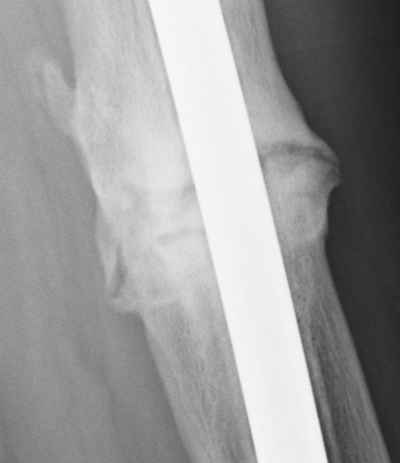

Jan. 31, 2006 Aug. 17, 2006 Apr. 17, 2007 Feb. 21, 2008